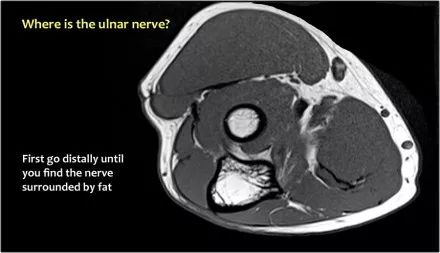

因此,当我们回到图像时,您会发现很难找到神经。任何这些皮下结构都可以是转位神经。一种方法是远端跟随结构,直到你发现远端的尺神经位于由脂肪包围的前臂近端的正常位置。然后当你向近端跟随它时,你会发现这是皮下移位。